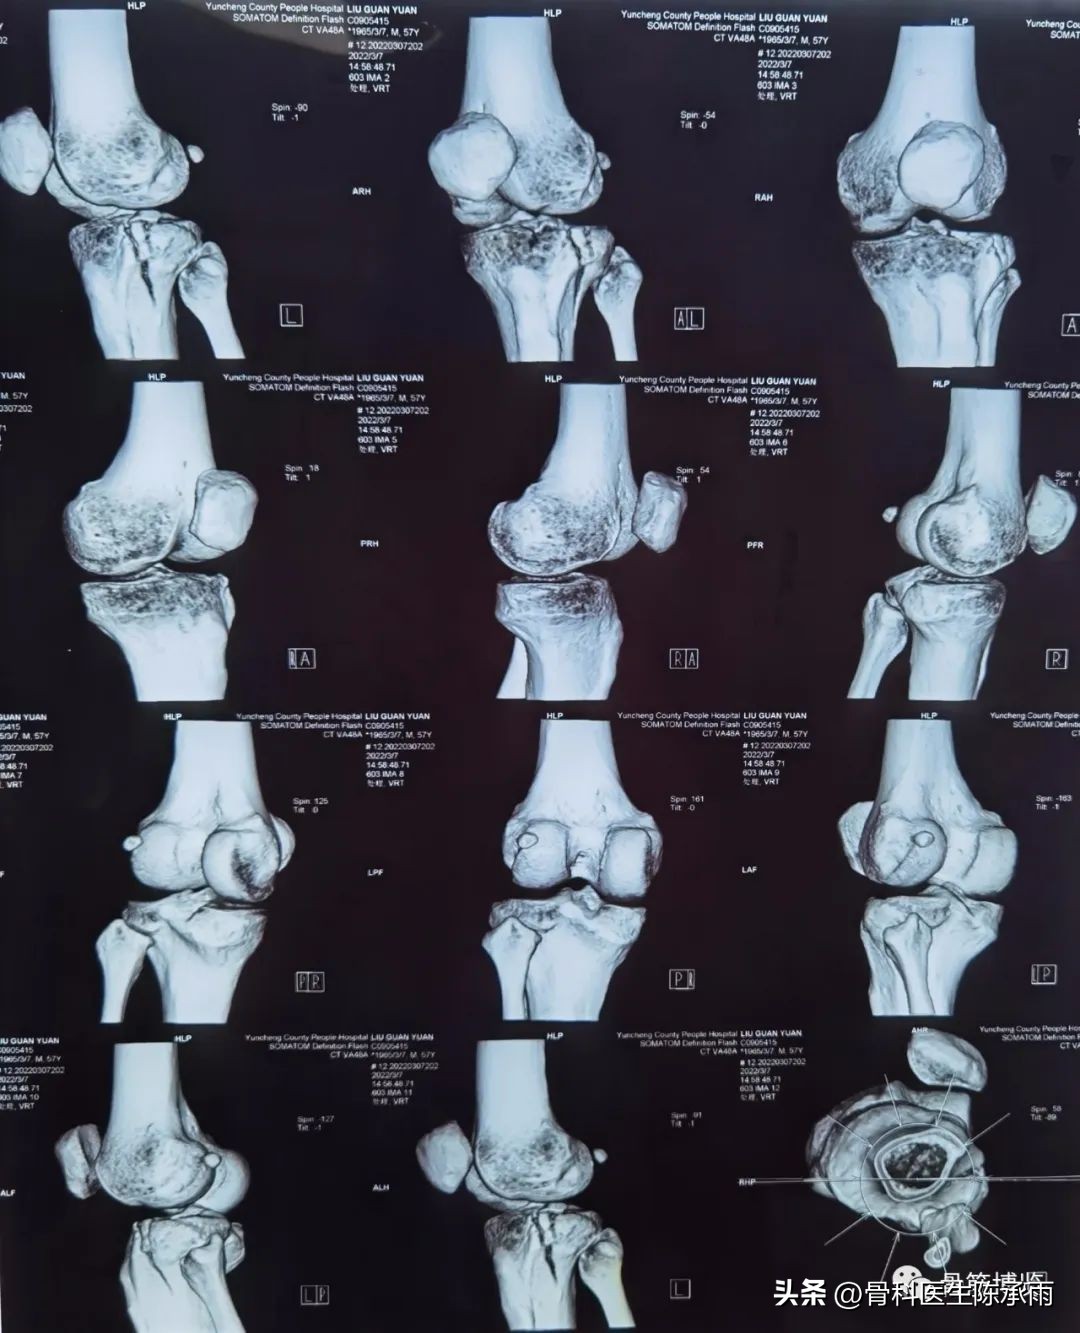

1例

2例

3例

4例

5例

6例

7例